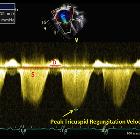

Echocardiography

When screening patients with a clinical suspicion of pulmonary hypertension, echocardiography findings can be used to grade the probability of elevated pulmonary artery pressures being present on right heart catheterization, as well as identify possible precipitants such as an atrial septal defect, valvular regurgitation or stenosis, or left ventricular diastolic dysfunction

The first measurement is the maximum velocity of the tricuspid regurgitant jet as observed from the apical four chambers, right ventricular inflow tract, or parasternal short (at the aortic valve level) axis views. The measured velocity informs one as follows:

- velocities >3.4 m/s are definitely abnormal, and the suspicion for pulmonary hypertension is high

- velocities below 2.8 m/s (or unmeasurable) and between 2.8 and 3.4 m/s require further measurements

- velocities <2.8 m/s (or unmeasurable) are stratified as low suspicion if there are <2 positive categories, and intermediate if there are 2 or more

- velocities between 2.8 and 3.4 m/s are either intermediate suspicion (<2 positive categories)

The ventricles (category A), pulmonary artery (category B), and right atrium and inferior vena cava (category C) may reveal suggestive findings of increased pressure/volume (a category is "positive" when one or more of the following findings are present).